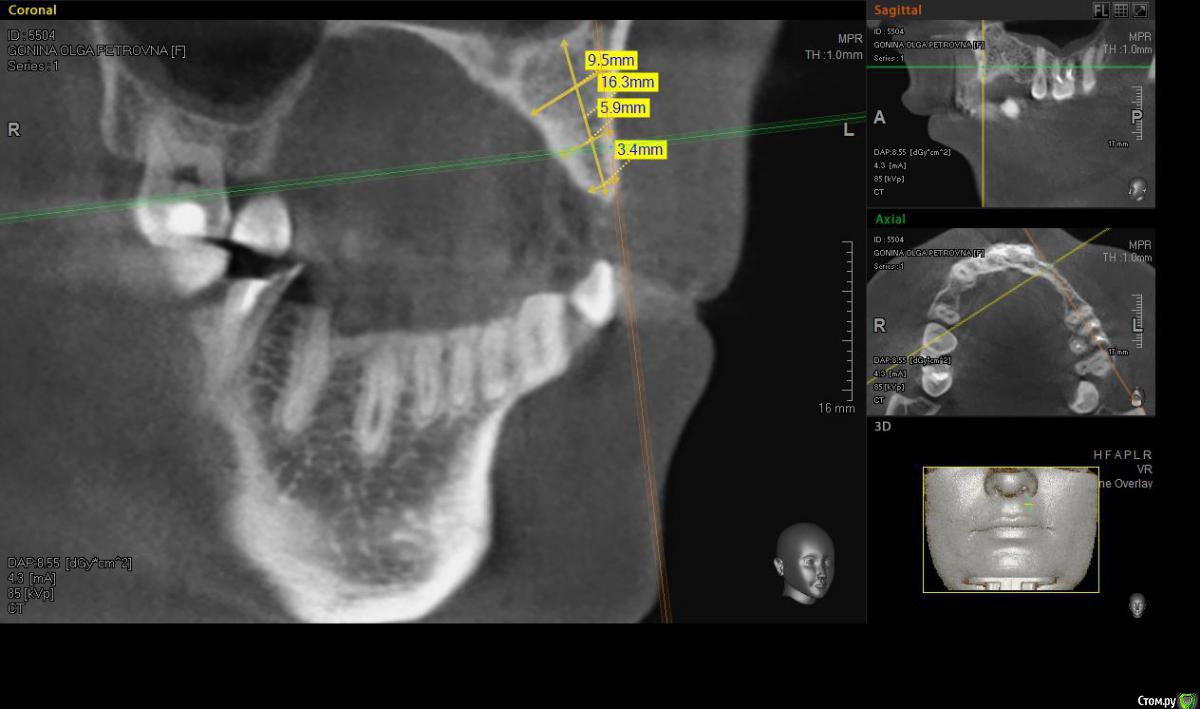

denis1987 Опубликовано 6 декабря, 2014 Поделиться Опубликовано 6 декабря, 2014 Здравствуйте, коллеги. У пациентки частичная вторичная адентия на верхней челюсти слева, отсутствующие зубы 22,23,24. С ортопедом запланировали имплантацию. Снимки прилагаю. Форма альвеолярного гребня вроде как то не особо располагает для расщепления, но все таки хочу попробовать. За ответы заранее спасибо. Ссылка на комментарий